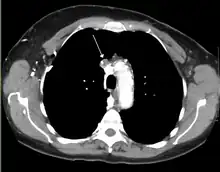

Diagnosis

The main techniques of diagnosing SVCS are with chest X-rays (CXR), CT scans, transbronchial needle aspiration at bronchoscopy and mediastinoscopy.[5] CXRs often provide the ability to show mediastinal widening and may show the presenting primary cause of SVCS.[5] However, 16% of people with SVC syndrome have a normal chest X-ray. CT scans should be contrast enhanced and be taken on the neck, chest, lower abdomen, and pelvis.[5] They may also show the underlying cause and the extent to which the disease has progressed.[5]